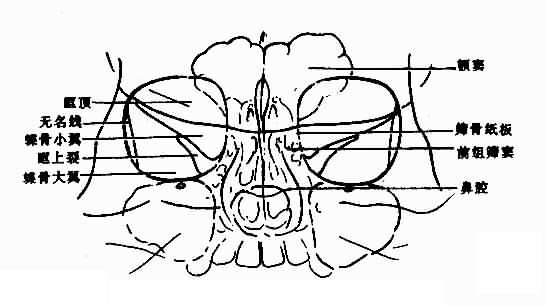

眼眶平片应观察:眶窝大小与形状,眶壁,包括眶顶、蝶骨小翼、蝶骨大翼、眶上裂、筛骨纸板(图5-2-1)等和眶窝密度,上述表现在两侧眼眶基本对称。

图5-2-1 正常眼眶(200后前位)

视神经孔:530后前斜位上,形近圆而略呈三角。边缘光滑整齐,密度较高。